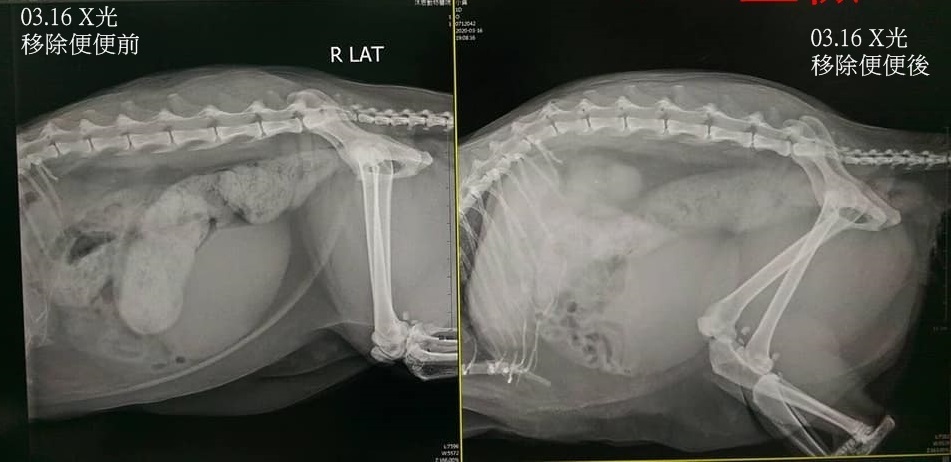

2020年3月小黃出現鼻涕淚眼,食慾也有下降,於3月11日至沐恩醫院檢查,體溫並無異常,體重也持平,醫師診斷可能是因天氣變冷所影響,開針對呼吸道用藥,希望減少鼻水可讓小黃舒服些也能增進食慾,服藥幾日後小黃鼻水減少,進食量也逐漸恢復,但3月13日小黃又出現無便情況,至3月16日已近4天沒有便便,因此再至沐恩醫院檢查,經X光檢查,看到腸道有許多積便,醫師給予鎮定後進行挖便,將多數便便挖出後,小黃先在醫院休息等待鎮定甦醒及觀察,稍晚狀況穩定即出院回到安養之家。

小黃可能是因為巨結腸症或是腎臟問題會造成排便困難,需要長期的醫療用藥及特別的飲食,本筆醫助是小黃在3月11日及3月16日至沐恩醫院的費用,包含X光、用藥及鎮定挖便,另為節省醫療費用,協會自行購買小黃每天要吃的腸蠕動劑、分裝膠囊及特別的進口腎臟處方乾飼料,請大家一起幫忙可愛的小黃,謝謝。

3/16 小黃 沐恩 袁醫師

一、看診情形

小黃已四天沒便而約診。

鎮定後挖出很多便便,但便便並不硬,醫師認為不是便便太硬造成積便,較可能是巨結腸症或腎病使得腸道蠕動功能不佳。

目前腸道多數便便已挖出,餘一些些小軟便可自行排出,這幾天會流一些糞水屬正常現象。